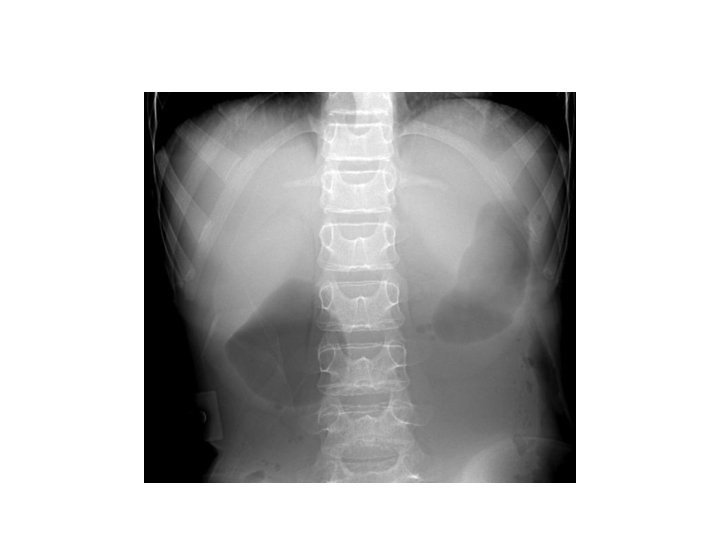

Duodenal Atresia • Commonest intestinal atresia • 1 in 10, 000 live births • Can occur in isolation or with other conditions like – Downs syndrome, – anorectal malformations, – CHD, – annular pancrease

Duodenal atresia • Vomiting, dehydration, jaundice, growth retardation • Fluids, electrolyte correction, nutrition(TPN) • Surgery: Duodenoduodenostomy, duodenostomy.